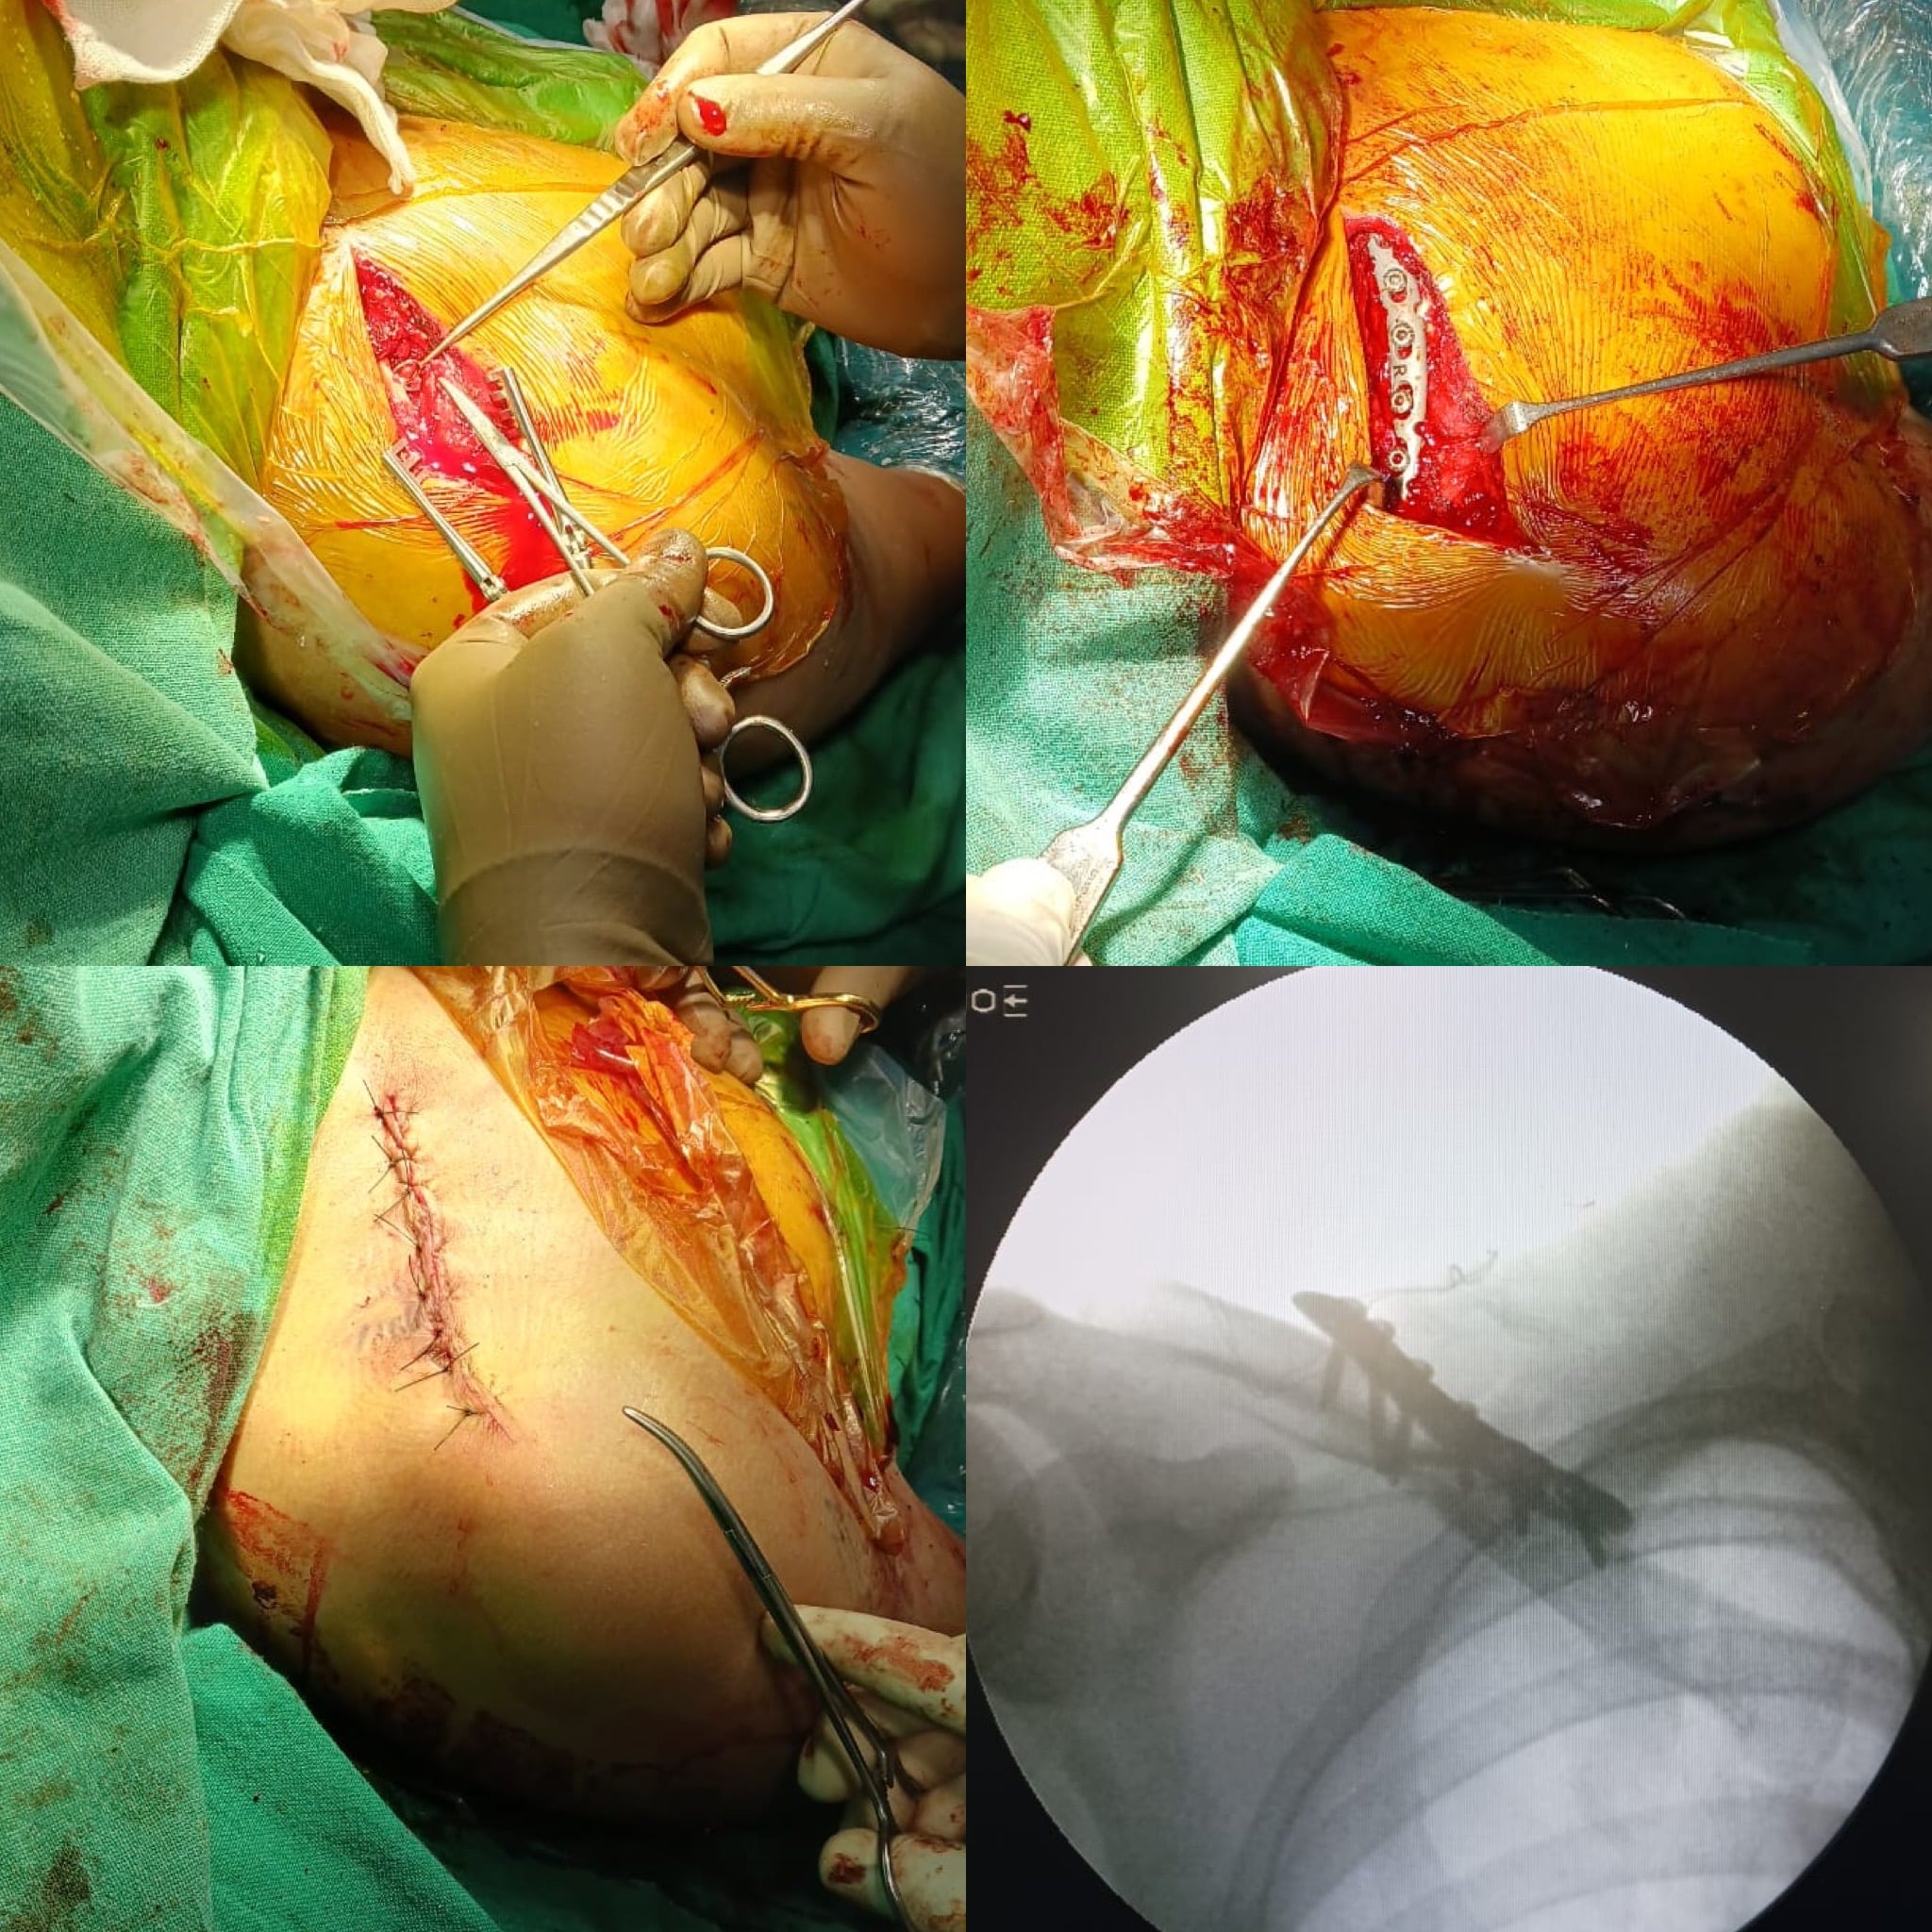

ORIF with Plating done in a right-sided post-traumatic case of comminuted displaced clavicle fracture